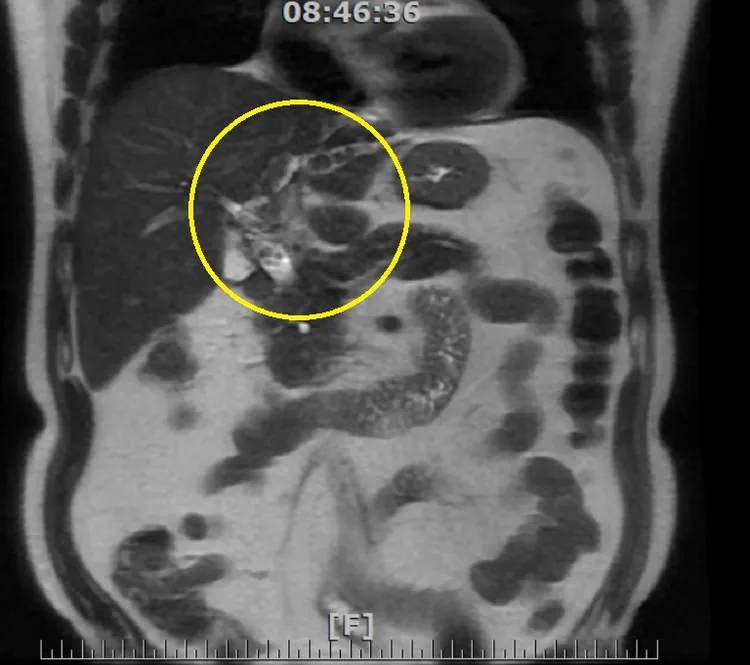

經核磁共振檢查影像,黃圈處可看出左肝、膽管及膽囊有結石。南投醫院提供

患者為68歲的劉先生,當時他就診時,醫生察覺到劉先生有黃疸、尿液顏色變深等問題,懷疑是肝臟出問題,經核磁共振檢查發現肝內膽管、膽管及膽囊,都有密密麻麻的結石,阻塞膽汁的運行,其中肝結石位於肝臟的左側位置,情況較為棘手。